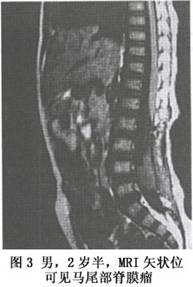

圖3 MRI 片1.脊柱X線平片 由於先天性腫瘤的長期壓迫使椎弓根變扁及椎管變寬,椎體後緣出現凹陷壓跡。椎管內胚胎組織源性腫瘤的患兒多合併有隱性脊柱裂或椎管閉合不全,啞鈴狀神經纖維瘤多有椎間孔擴大,硬脊膜外腫瘤常有椎體或椎弓根骨質的破壞。

3.MRI檢查 脊髓的MRI矢狀位成像可不受脊椎生理彎曲的影響,充分連續的顯示脊髓的全長及椎管前後緣的關係,更好的確定病變的解剖界限;冠狀位可觀察脊髓兩側的神經根和脊髓的形狀 以鑑別髓內髓外病變及其範圍(圖2,3);而且MRI對脊髓內病變的信號特徵顯示也優於CT,是椎管內病變的首選檢查措施。